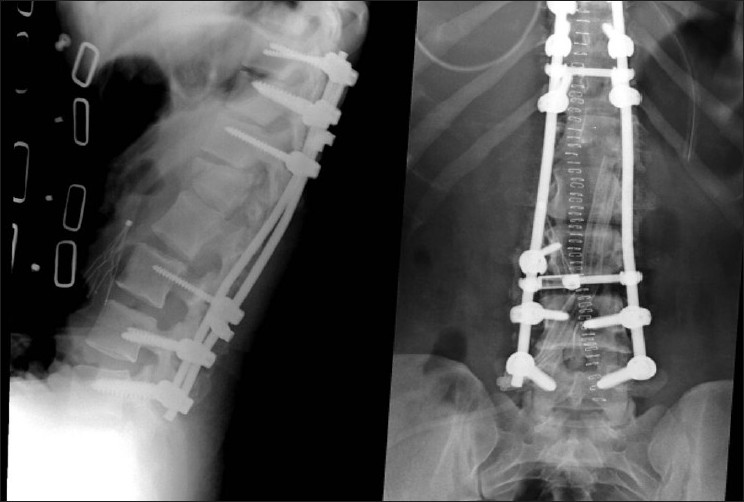

This patient's postoperative management was routine for a patient with severe spinal injury. She was transferred to the floor following the recovery room. The incision healed without any complications or any spinal fluid-related issues. Radiographically, postoperative x-rays and a CT demonstrated excellent alignment and placement of pedicle screw instrumentation [Figure 5]. The patient was fitted with a Thoracolumbosacral orthosis (TLSO) brace on postoperative day 1. Rehabilitation was initiated on postoperative day 1. Over the course of a week, the patient's examination improved to American Spinal Injury Association (ASIA) C with antigravity strength at the iliopsoas. The patient continued to improve in rehabilitation over the following months. | Figure 5: Postoperative AP and lateral X-rays showing good alignment, reduction of the subluxation, and instrumentation

Click here to view |